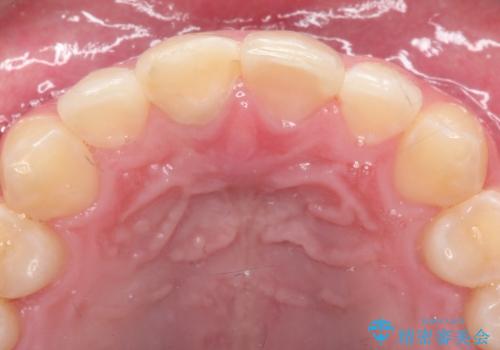

- 右上1番の色が暗いのを主訴に来院されました。

失活歯(神経の治療をしている歯)の場合、薬剤を歯の表面に塗布するホワイトニングでは白くなりません。歯の中に薬剤を入れて薬剤の反応を待つ必要があります。

治療手順としましては、マイクロスコープ(歯科用顕微鏡)を使用し、元々入っていた詰め物のCR(プラスチック)を除去します。その後、歯の中に薬剤を入れ、蓋をします。2週間後に来院して頂き、白くなっているかを確認します。ご本人がご満足頂く白さになるまで、これを3~4回繰り返します。今回は1回で患者様がご満足されたので治療を終了しています。